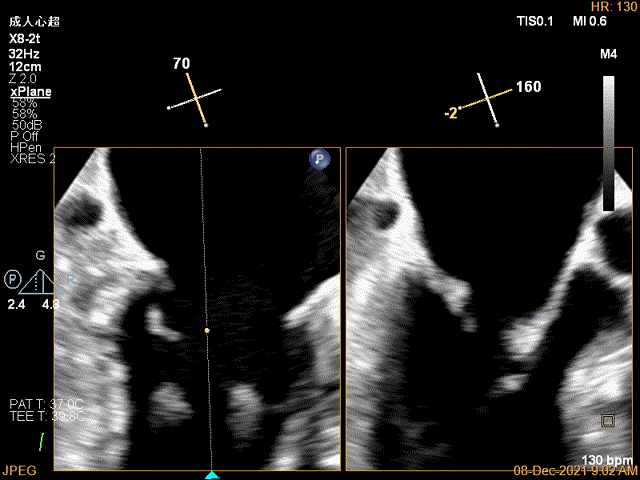

2D视图下trajectory

2D视图下开夹子

X-plane:下夹子尝试先捕获2区瓣叶